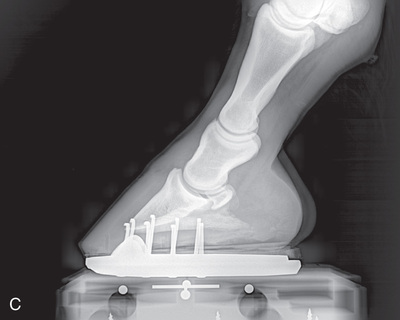

A cassette tunnel is also useful for digit radiographs to protect the image receptor for dorsopalmar/dorsoplantar and oblique views of the foot. A cassette tunnel can be purchased or can be manufactured out of radiolucent wood (avoid use of nails) or hard plastic durable enough to withstand the weight of the horse. If using a cassette tunnel, make sure it is strong enough to support the weight of the horse and is translucent to minimize artifacts on the film (Fig. 24.4F and G). To minimize a slippery surface, cover with duct tape or use a mouse pad or section of yoga mat between the hoof and tunnel.

If using a foot block, have it high enough so that the beam can be directed in a horizontal plane on the area of interest. Ideally, the block should have a slot to support the cassette close to the limb to minimize distortion (Fig. 24.4D). If only the lateromedial view of the digit is needed, then shoe removal, sole cleaning, and foot trimming are not essential. For equal weight-bearing, both front feet should be on a foot block. If only the affected foot is placed on the block, improper pressure of the distal limb joints may affect the accuracy of the diagnosis.